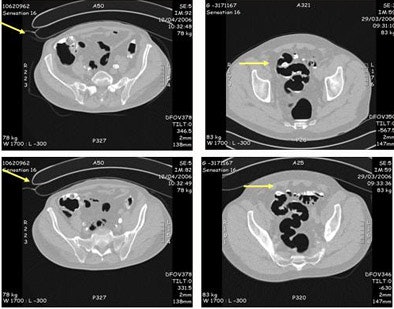

![]() |

| The results showed high sensitivity, specificity, and negative predictive value for tagged prepless virtual colonoscopy, particularly among lesions 8 mm or larger in diameter. Chart courtesy of Dr. Didier Bielen. |

For lesions 8 mm and larger, VC's specificity and sensitivity (positive and negative predictive values) were 91% and 99%, respectively, Bielen said, and 100% for lesions 10 mm and larger.

A previous study by Iannacone et al from the University of Rome in Italy yielded 92% sensitivity for polyps 8 mm or larger for prepless VC in an average-risk cohort of 180 patients.

"We conclude that (VC) using water soluble tagging agents is feasible in daily practice," Bielen said. "It gives you acceptable tagging for residual fluid, but poses a problem for residual stool. Nonetheless promising results (showed) high specificity and sensitivity and negative predictive values, especially for lesions above 8 mm."